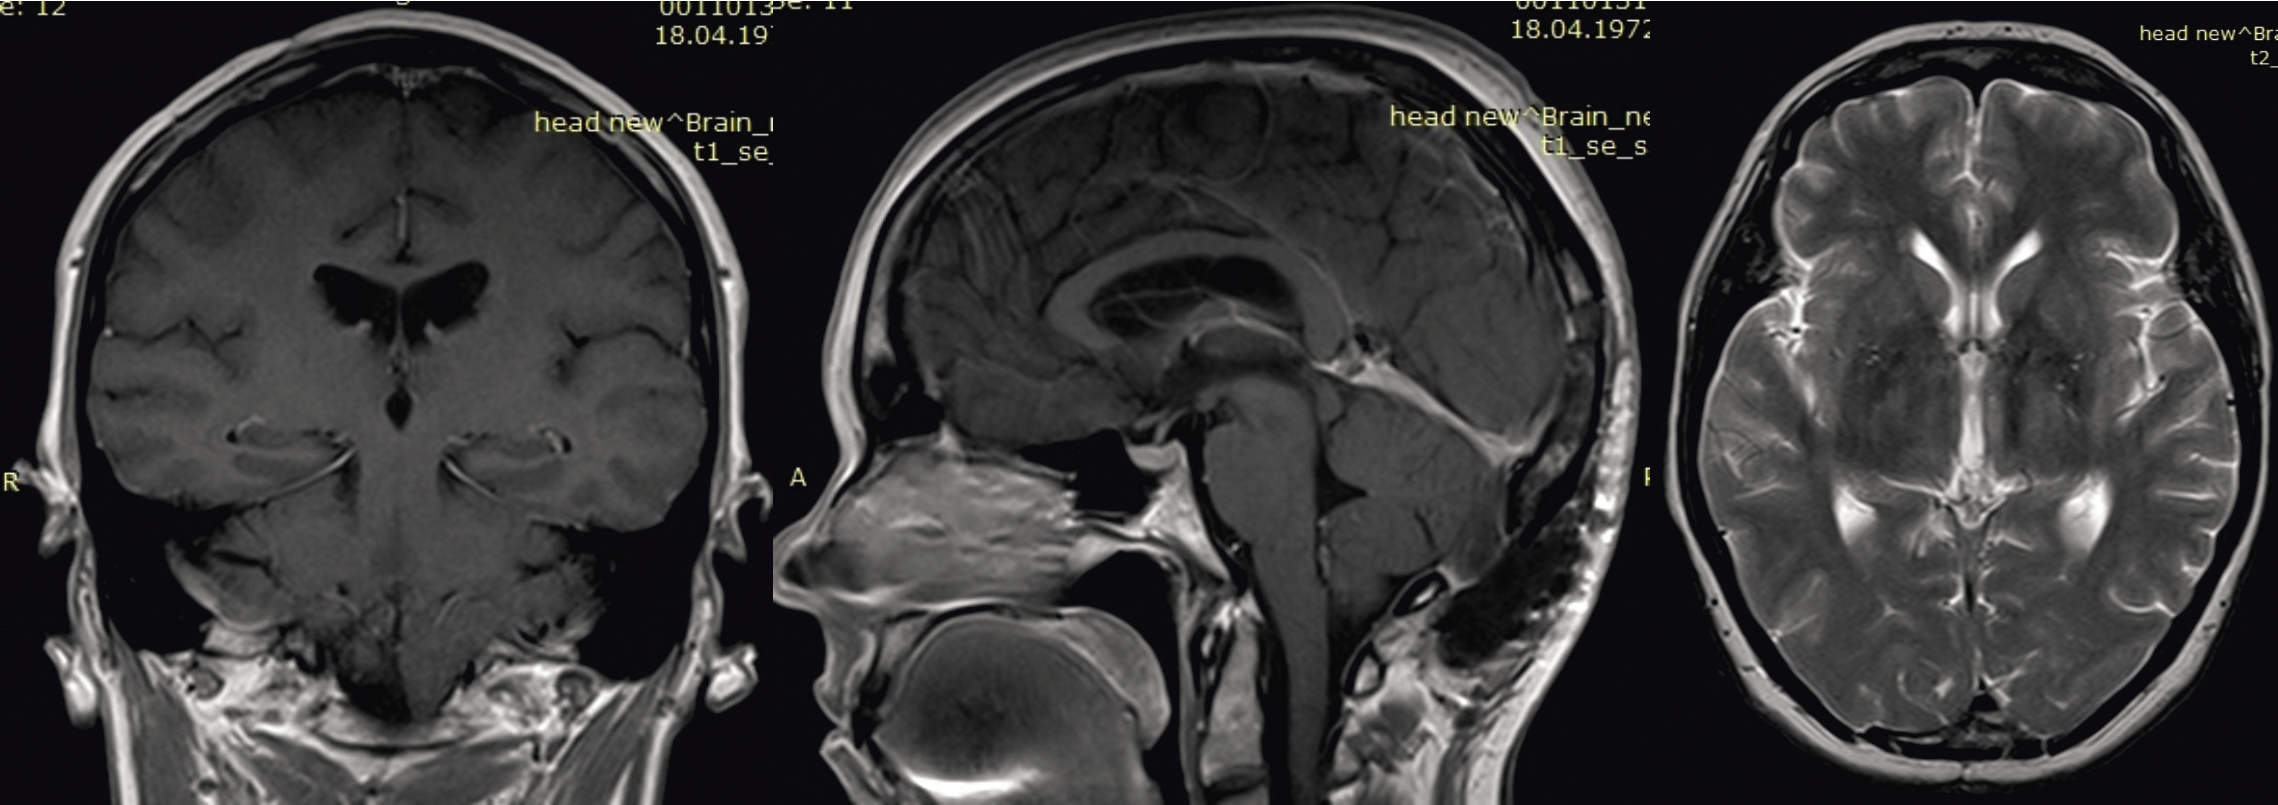

Приводим данные контрольного МРТ-исследования больной спустя 6 месяцев после операции и курса локальной лучевой терапии (нет признаков рецидива опухоли в зоне удаления, ликворопроводящие пути свободные) (рис. 2).

Рис. 2. МРТ головного мозга спустя 6 месяцев после операции и комплексного онкологического лечения